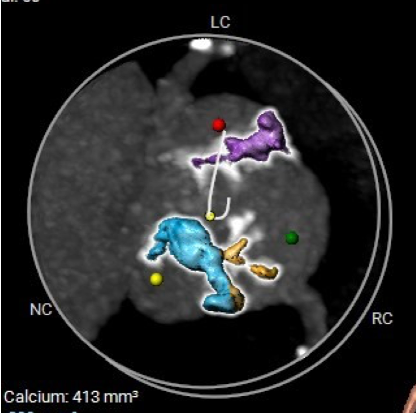

CT数据显示该患者为Type1型主动脉瓣。

钙化分布:HU850钙化积分413mm³